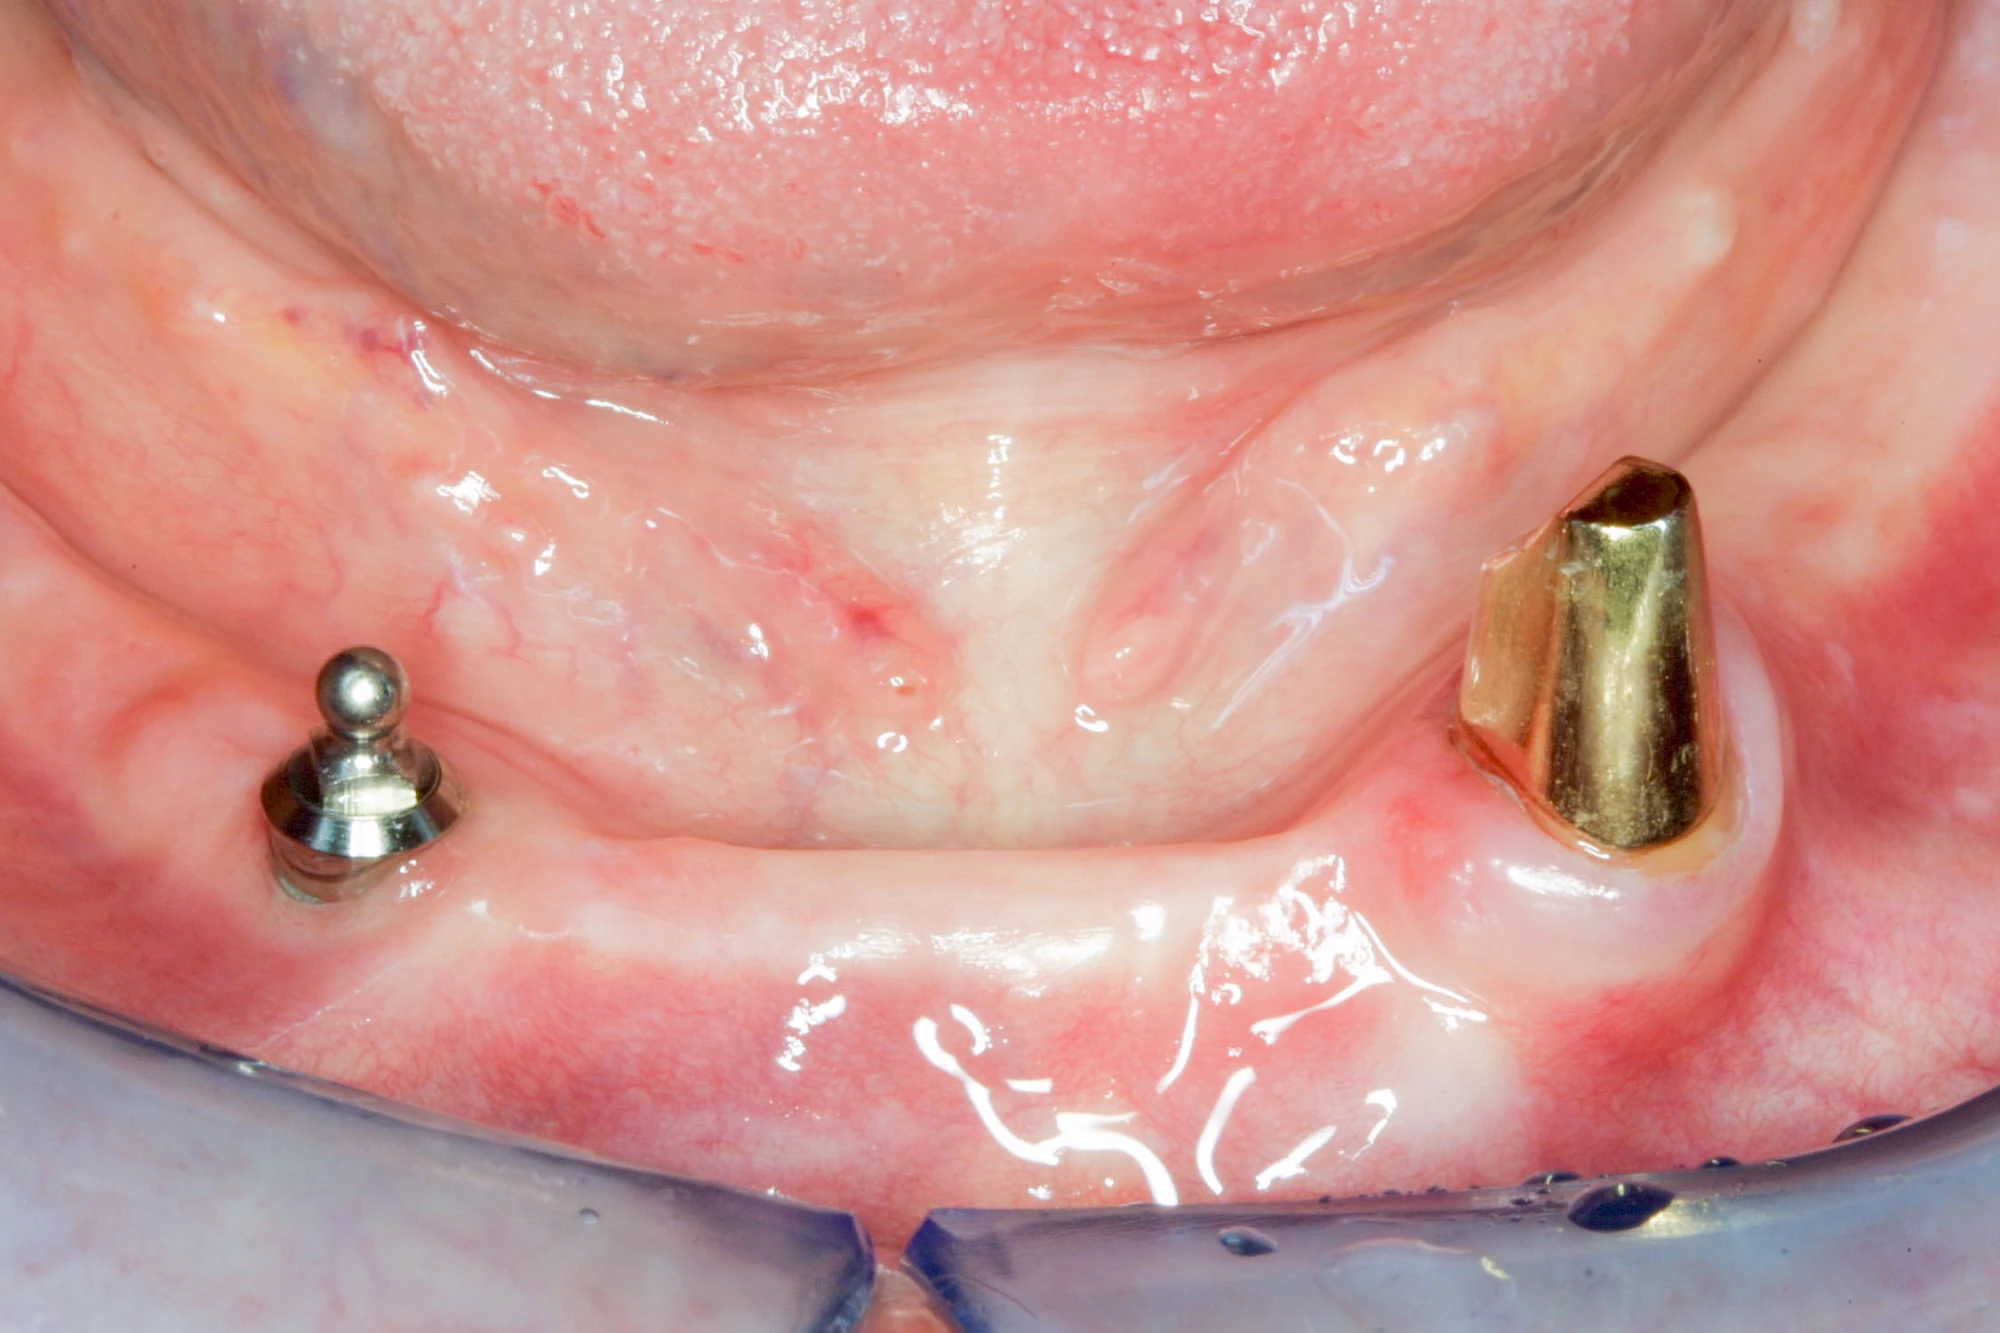

Bei herausnehmbaren Prothesen werden Implantate eingesetzt, um den Halt und den Tragekomfort der Prothesen zu verbessern. Dazu kommen verschiedene Verbindungselemente zum Einsatz:

- Teleskope

- Kugelköpfe

- Tellerförmige Lokatoren

- Stege

- Magnete (selten)

Neben rein implantat-getragenen zahnärztlichen Versorgungen werden bei herausnehmbaren Prothesen Implantate auch in Sinne einer "strategischen Pfeilervermehrung" ergänzend zu eigenen Zähnen zur Verankerung eines Zahnersatzes genutzt.

Varianten zur Verankerung von abnehmbarem Zahnersatz auf Implantaten